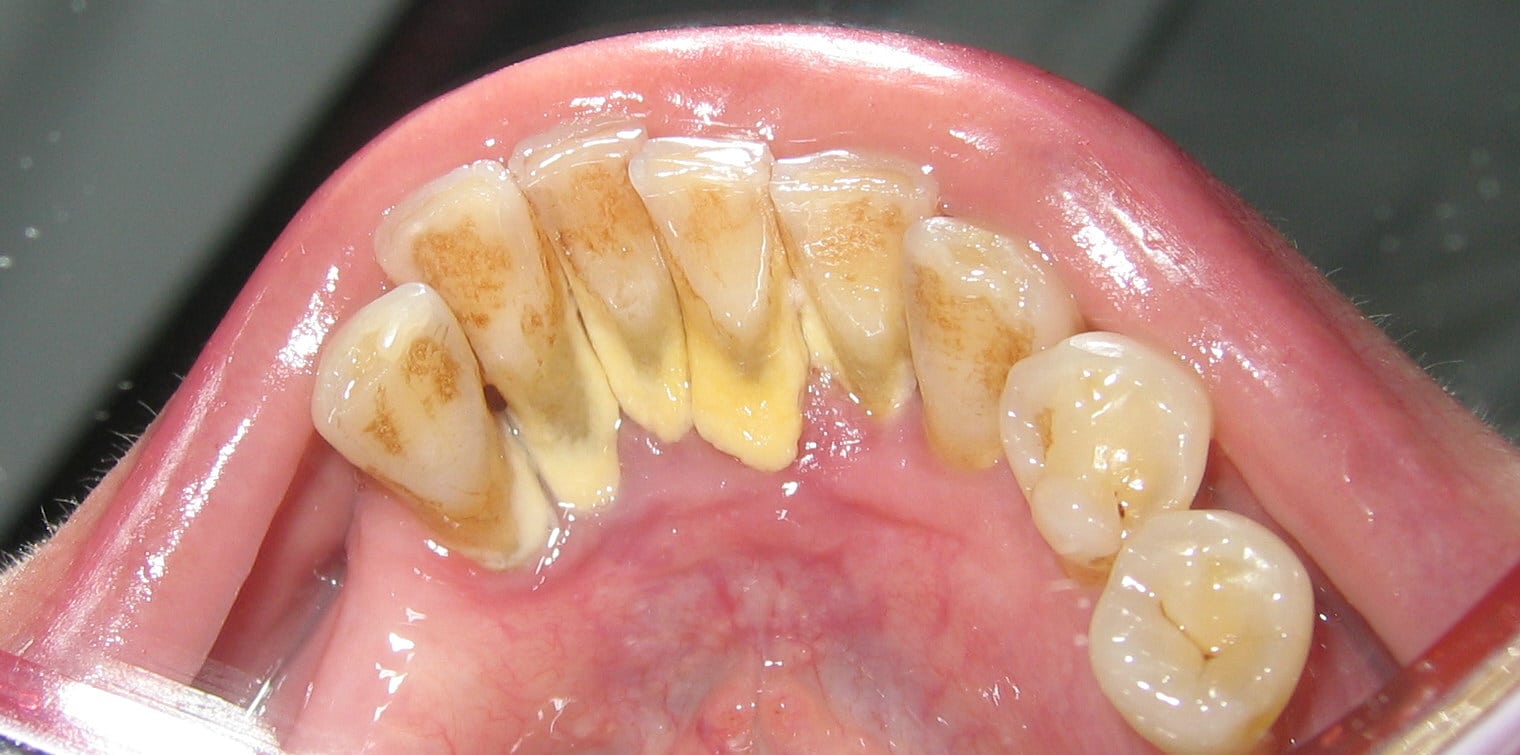

Tartar (also known as dental calculus) occurs on the teeth when plaque How To Remove Tartar With Dental Pick Brushing is an important way to remove plaque and reduce the bacteria in your mouth. Only a dental professional will be able to remove tartar from your teeth once it has formed. This guide explains how best to handle tartar at home, from routine care to diy treatment methods, as well as why these cannot replace. However, remedies such as. How To Remove Tartar With Dental Pick.